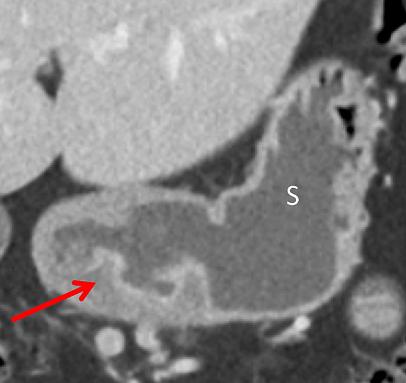

中年男性,突发吞咽困难。冠状位 CT 增强静脉期示胃体部位置上移至幽门上方,食管胃连接处位置仍正常。